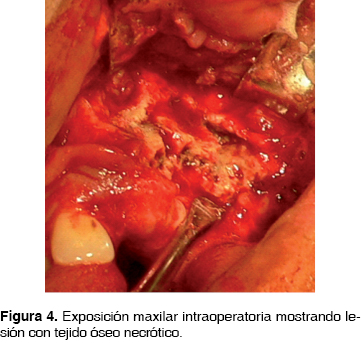

Se inicia manejo con clindamicina 600 mg IV cada 8 h y ceftriaxona 1 g IV cada 12 h. A continuación, bajo anestesia general inhalatoria balanceada, se realiza hemimaxilectomía subtotal, mediante abordaje circunvestibular durante el procedimiento se observan áreas óseas líticas y necróticas (Figura 4) , se procede a la resección de la lesión obteniendo un espécimen quirúrgico de 2 x 4 cm. Se sutura con ácido poliglicólico 3 ceros. Se envía la pieza quirúrgica a patólogo oral que reporta osteomielitis crónica maxilar con bordes libres de lesión, continúa durante 30 días con penicilina G procaínica 800,000 UI IM cada 24 h por 30 días. En la actualidad se encuentra clínica e imagenológicamente sin datos de recidiva (Figuras 5 y 6).